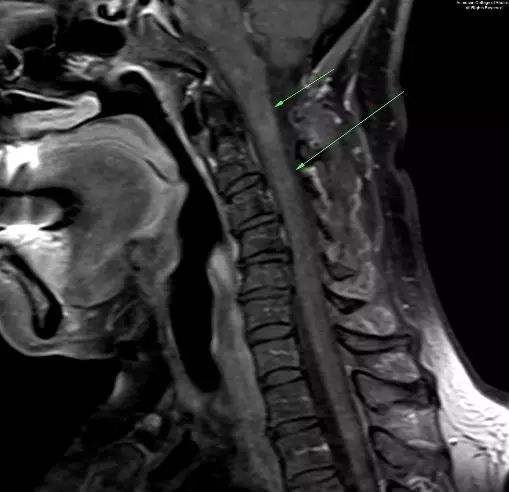

图 4. 矢状增强T1示颈椎内异常强化灶,范围从C1水平到C4下方(箭头示)

图 5. 矢状T2示C1到C4下方水平颈椎内脱髓鞘病灶(箭头示)